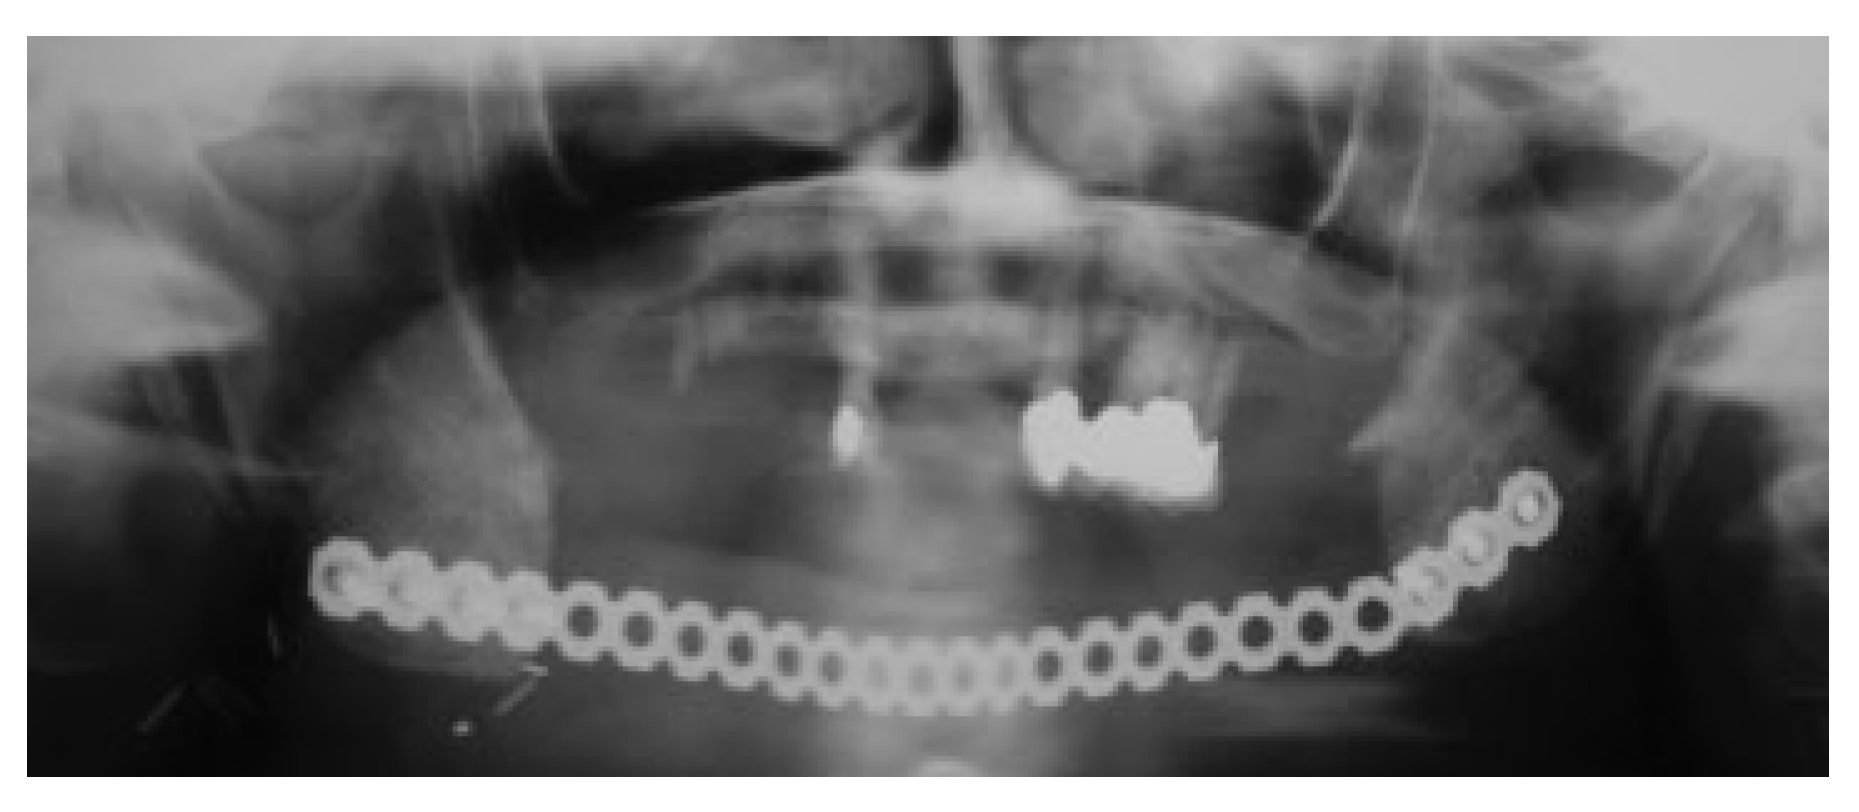

Usually 3 to 6 months after soft tissue reconstruction, the resection site is re-entered from a submandibular approach and dissected, by identifying the plane between the two layers of the muscle wrap to open a recipient site pouch. Figure 4 shows en example of an extensive resection with immediate insertion of a reconstruction plate and a LD flap. Six months later, the resection stumps were exposed, and the defect was grafted with a strut of cortical bone that acts as a sheet pile wall for the particulate corticocancellous bone harvested from the ileum. Platelet-rich autologous fibrin glue may be added to help containment and molding of the bone graft mass [14] (Figure 5).

Endosseous dental implants were installed in the reconstructed area for successful implant fixed dental restoration in three patients (nos. 6, 12, and 14). The remodeling of bone during healing and function of the reconstructed mandible seemed to enhance a change of morphology of the grafted corticocancellous and particulate bone into a tubular bone with an outer cortex very similar to the pristine mandible. Whereas the grafted bone followed the mandibular horseshoe shape when grafted to the anterior region (Figure 5, Figure 6 and Figure 7), a reconstruction of the angle of the mandible proved more problematic with this technique as functional remodeling tends to lead to a straight bony connection uniting the resection stumps.

There are pros and cons with either mode of reconstruction, microvascular, and free bone grafting. The AO Manual of Internal Fixation in the Cranio-Facial Skeleton advices that very large defects may be reconstructed with microvascular grafts, whereas smaller defects may be repaired with cancellous bone from the iliac crest [26]. Some authors consider the maximum length of a segmental mandibular gap to be grafted with a nonvascularized bone graft to be 4 to 6 cm. This limit was considerably surpassed in our case no. 6) shown in Figure 4 and Figure 5. Conversely, a fibula reconstruction for a defect less than 4 cm may be overdoing fibula reconstruction, and very short segments of fibula may suffer a critical blood supply depending on the location of perforators. Furthermore, mandibular height in dentate regions of the mandible is not easily achieved with a fibula, unless a double barrel reconstruction is performed [27]. Adequate mandibular height will provide a vertical and transverse jaw relation to favor position and bony support for dental endosseous implants and offer conditions for sufficient oral hygiene. Fixed or removable prostheses will aid speech and mastication, allowing patients to regain their physical appearance and social function, thus leading to a better quality of life.

Figure 4. Case of extensive segmental resection with simultaneous mandibular plate reconstruction and soft tissue repair with latissimus dorsi myocutaneous flap.

Figure 5. Reentry with grafting of cortical bone struts and particulate corticocancellous bone from posterior iliac crest.